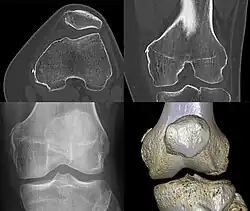

Diagnosis is typically made on radiographs demonstrating the Pellegrini-Stieda syndrome sign accompanied by pain or restriction of range-of-motion of the knee joint.[2] Pellegrini-Stieda syndrome sign is typically described by a longitudinally linear opacity, which is a process that is describes characteristic of calcification in the soft tissue located medial to the medial femoral condyle.[2] This calcification seen on imaging represents the ossification of the medial collateral ligament, which typically does not develop until approximately three weeks after the initial injury.[2]It is important to note to distinguish this radiographic finding from that of a medial femoral condyle avulsion fracture, which is an injury in which a pulling force of a tendon or ligament fractures away a piece of the bone from its attachment site.[2]

Alternative classification syndrome for Pellegrini-Stieda lesions of Type 1 through Type 4 based on their location:[2]

- Type 1- is referred to as a beak-like appearance and describes the ossification arising from the femur and extending inferiorly in the medial collateral ligament.

- Type 2-is defines a tear-drop pattern, localized within the medial collateral ligament without any attachment to the femur.

- Type 3-presents as an elongated ossification superior to the femur lying in the distal adductor magnus tendon.

- Type 4-is also characterized as a beak-like appearance arising from the femur. However, there are some cases where this ossification extends into both the medial collateral ligament and adductor magnus tendon. In then, the original attribution of the syndrome to the medial collateral ligament may now be outdated as many publications have suggested concomitant and even sometimes preferential involvement of the adductor magnus tendon, medial head of the gastrocnemius, or medial patellofemoral ligament.[2]

Lastly, another case was presented to investigate the origin of the Pellegrini-Stieda lesion using radiography. They used six non-paired fresh-frozen cadaveric knees. A surgical approach to the medial side of the knee was performed using the layered approach. X-Ray analysis was performed by measuring the distance from the proximal part of the marking to the medial tibial plateau, multilayered views and comparison to the original X-rays by Pellegrini-Stieda. Conventional X-ray of the knee could not reproduce the historic distinction between the Pellegrini and the Stieda origins for the Pellegrini-Stieda lesion. There has been debate where the origin of the Pellegrini-Stieda Lesion remain lively, although recent studies have suggested other possible origins, such as the Adductor Magnus muscle in addition to the MCL. There have been limitations to present studies like limited number of specimens, more reliable results, questionable X-ray information as the technique used by Stieda and Pellegrini have been shown to have a lack of detail as they are historic publications.[3]